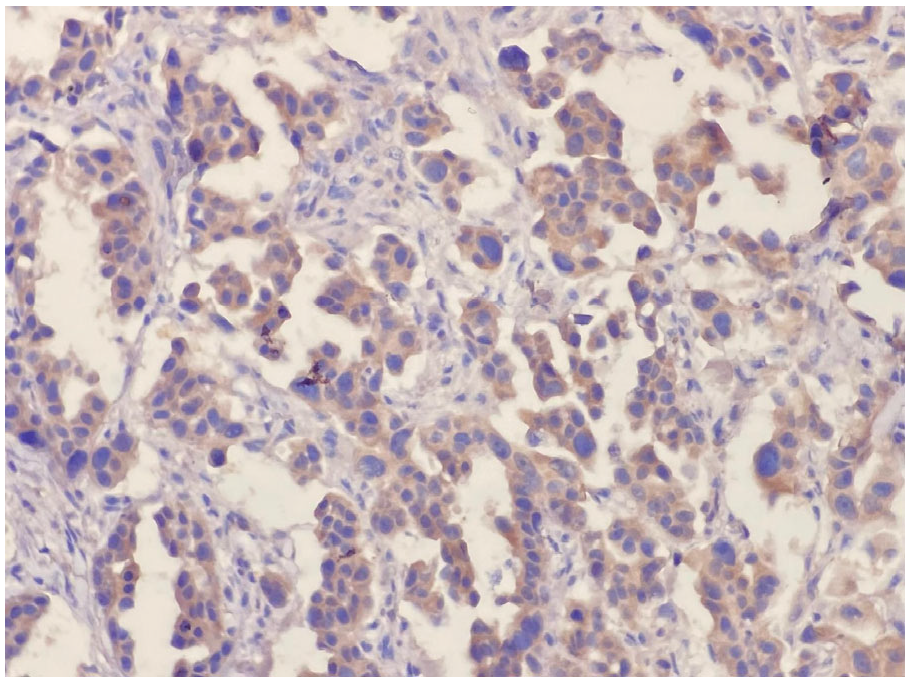

During HER-3 immunohistochemical staining evaluation, both positive and negative controls were taken into account. Staining in more than 30% of tumor cells was considered positive, consistent with the positivity threshold applied in previously published immunohistochemical studies evaluating HER3 expression in NSCLC [20,22]. Evaluation was based on membranous staining intensity. Weak membranous staining was scored as 1, complete but moderate membrane staining was scored as 2, and complete and strong staining was scored as 3 (Figure 1 and Figure 2). HER3 immunohistochemical evaluation was performed by two experienced pathologists with expertise in thoracic pathology at our center. The staining results were independently reviewed and scored according to predefined criteria, and any discrepancies were resolved by consensus. Formal interobserver agreement was not statistically assessed, which represents a limitation of the study.

Figure 1.

Complete membranous strong reaction, score 3 (×400).